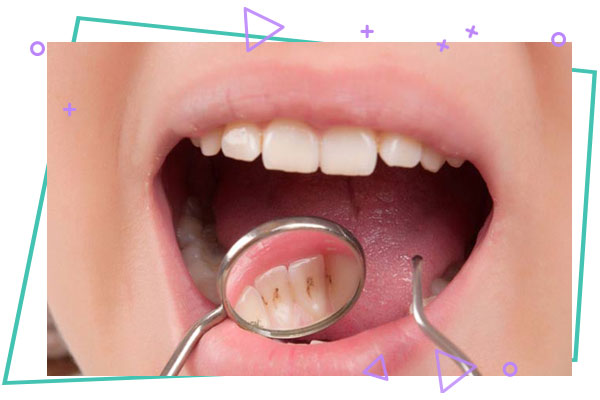

جرمگیری و تمیزکردن دندان

جرمگیری و تمیزکردن دندان : جرم دندان لایه ای زرد و سفت از میکروب ها و مواد غذایی است که به مرور زمان روی دندان